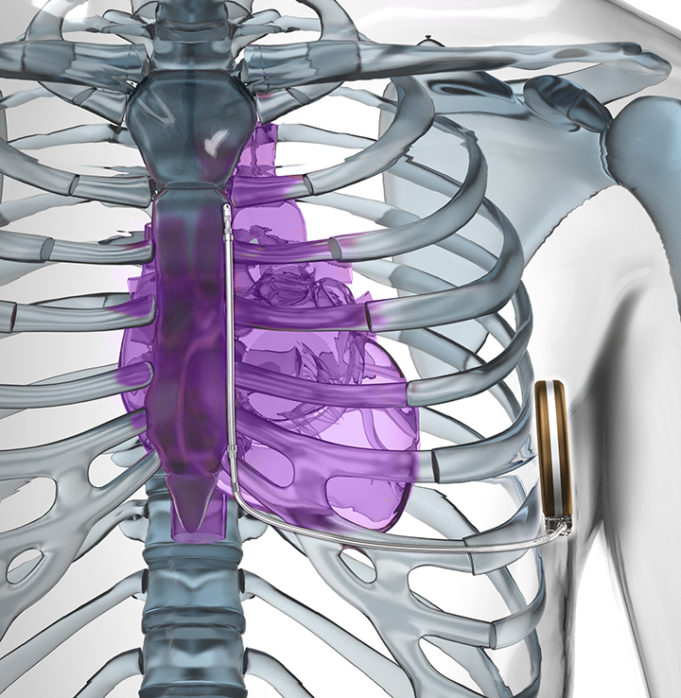

This advertorial has been sponsored by Boston Scientific

Two landmark studies have been published in 2020 following the use of subcutaneous implantable cardioverter defibrillator (S-ICDs) as a primary prevention therapy for sudden cardiac death. Cardiac Rhythm News speaks to the...

Subcutaneous implantable cardioverter defibrillators (S-ICDs) are as protective as transvenous implantable cardioverter-defibrillators (ICDs) in the prevention of sudden cardiac death, but have a better safety profile, the results of a prospective, randomised trial online in a late-breaking trial session...